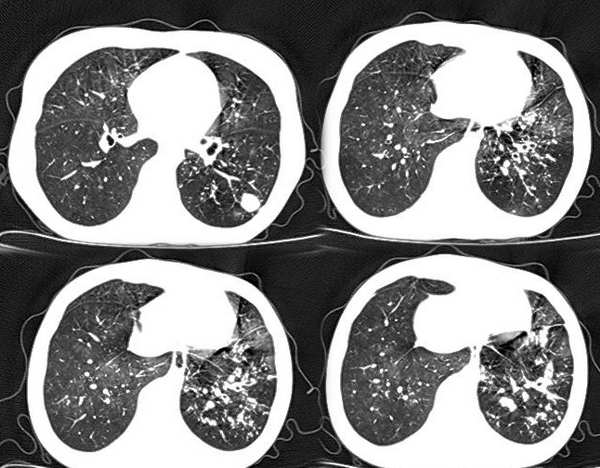

以下是引用x线在2006-2-2 17:37:00的发言:[br]结合病史支持“ct拟诊:双侧tb,左下叶结核球,左下叶局限性轻度支扩。”双下叶及左舌叶淡薄的毛玻璃密度影,我考虑为炎性渗出。另:是否合并霉菌感染须进一步检查确定。